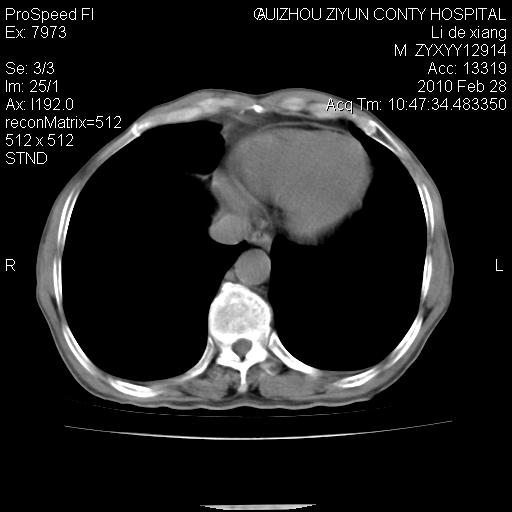

标题: CT24776:男 71Y 咳嗽咳痰胸痛两月,伴声音嘶哑。 [打印本页]

标题: CT24776:男 71Y 咳嗽咳痰胸痛两月,伴声音嘶哑。

左侧中央型肺癌伴左肺上叶阻塞性肺炎及节段性不张可能性大,建议纤支镜检查!

左侧中央型肺癌伴左肺上叶阻塞性肺炎及节段性不张可能性大,建议纤支镜检查!纵隔淋巴结转移.

左肺门部肿块,伴左上肺斑块影,周边模糊,支持左肺中央型肺癌伴节段性不张及阻塞性肺炎,结合支气管镜检查。

左上叶支气管狭窄,阻塞性病变,肺门肿块,纵隔及肺门淋巴结增大,中央性肺癌

左肺中央型肺癌并阻塞性改变、纵膈 淋巴结转移